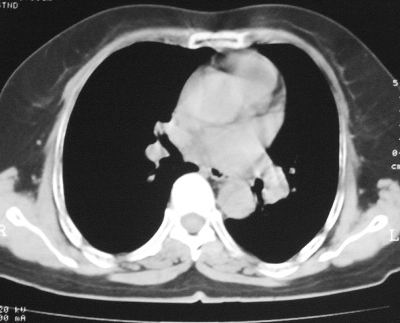

患者,女,64岁,4年前左腮腺"多形性"腺瘤手术治疗史.现复查胸部ct见左下肺块状影,该影与原左腮腺手术是否有联系?

本次复查胸部ct

左下肺癌伴左肺门淋巴结转移

支持考虑左下肺原发性肺癌,并左肺门淋巴结肿大

左下周围型肺癌伴左肺门淋巴结及右肺转移可能性大.